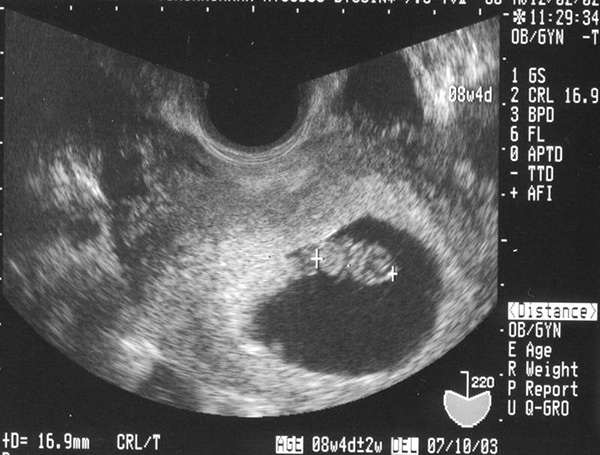

Trong thời gian trứng rụng nếu gặp tinh trùng chúng sẽ kết hợp với nhau ở vòi trứng sau đó di chuyển đến ống dẫn trứng. Khi kết hợp với nhau chúng không di chuyển vào trong tử cung ngay mà khoảng 4 đến 5 ngày sau đó chúng mới tiến hành di chuyển vào tử cung.

Khi chúng di chuyển vào tử cung chúng luôn có những dấu hiệu thai vào tử cung rõ ràng để chị em theo dõi. Những biểu hiện đó là gì? Các bạn hãy cùng tham khảo qua những chia sẻ tiếp theo đây.